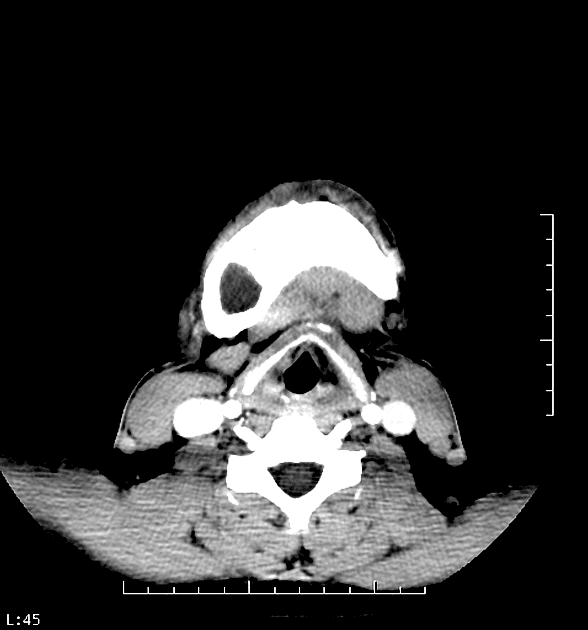

| Ghi nhận mở rộng của các xương | Xương trán, xương ethmoidal, xương hàm trên và xương chùm ngải kèm các thành phần nang không đồng nhất bên trong. |

| Chèn ép dây thần kinh thị giác | Chèn ép dây thần kinh thị giác hai bên (phải > trái). |

| Dịch chuyển não | Dịch chuyển phía sau của thùy trán phải. |

| Tăng quang sau tiêm chất tương phản | Tăng quang không đồng nhất sau tiêm gadolinium tĩnh mạch. |

Hình ảnh MRI phù hợp với xơ xương sọ mặt, đặc trưng bởi:

- Bất đối xứng sọ.

- Mở rộng và thay thế xương bình thường bằng mô sợi.

- Độ tín hiệu không đồng nhất do có các khu vực nang.

- Tăng quang không đồng nhất sau tiêm IV gadolinium.

- Dây thần kinh thị giác phải bị kéo dài.

rối loạn sợi xơ dạng xơ sọ mặt (Craniofacial fibrous dysplasia)